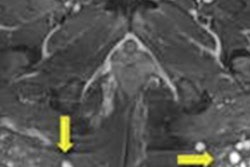

Identification of several visual patterns of collapsed and folded elastomer shell floating in gel: "linguine," "keyhole," "teardrop," "inverted teardrop," and "noose" signs depict silicone visible both inside and outside a radial fold. Image courtesy of Marike Maijers.

Identification of several visual patterns of collapsed and folded elastomer shell floating in gel: "linguine," "keyhole," "teardrop," "inverted teardrop," and "noose" signs depict silicone visible both inside and outside a radial fold. Image courtesy of Marike Maijers.A prospective cohort study out of the Netherlands included 107 women with 214 PIP silicone implants who underwent explantation preceded by short-tau inversion recovery (STIR) MRI. Most of the patients were asymptomatic (70%), and all patients had not previously visited a doctor -- the women wouldn't have been seen if it weren't for the recall, according to Marike Maijers, a doctoral student and resident in plastic surgery at VU University Medical Center in Amsterdam. Maijers wrote her thesis on safety in the imaging of silicone breast implants, with a particular focus on PIP implants.